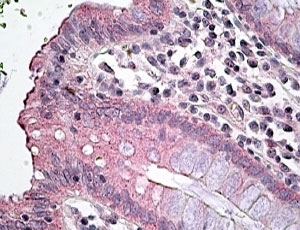

Amino acids NALQHSIRLSGVEDH were used as the immunogen for this SLC12A2 antibody.